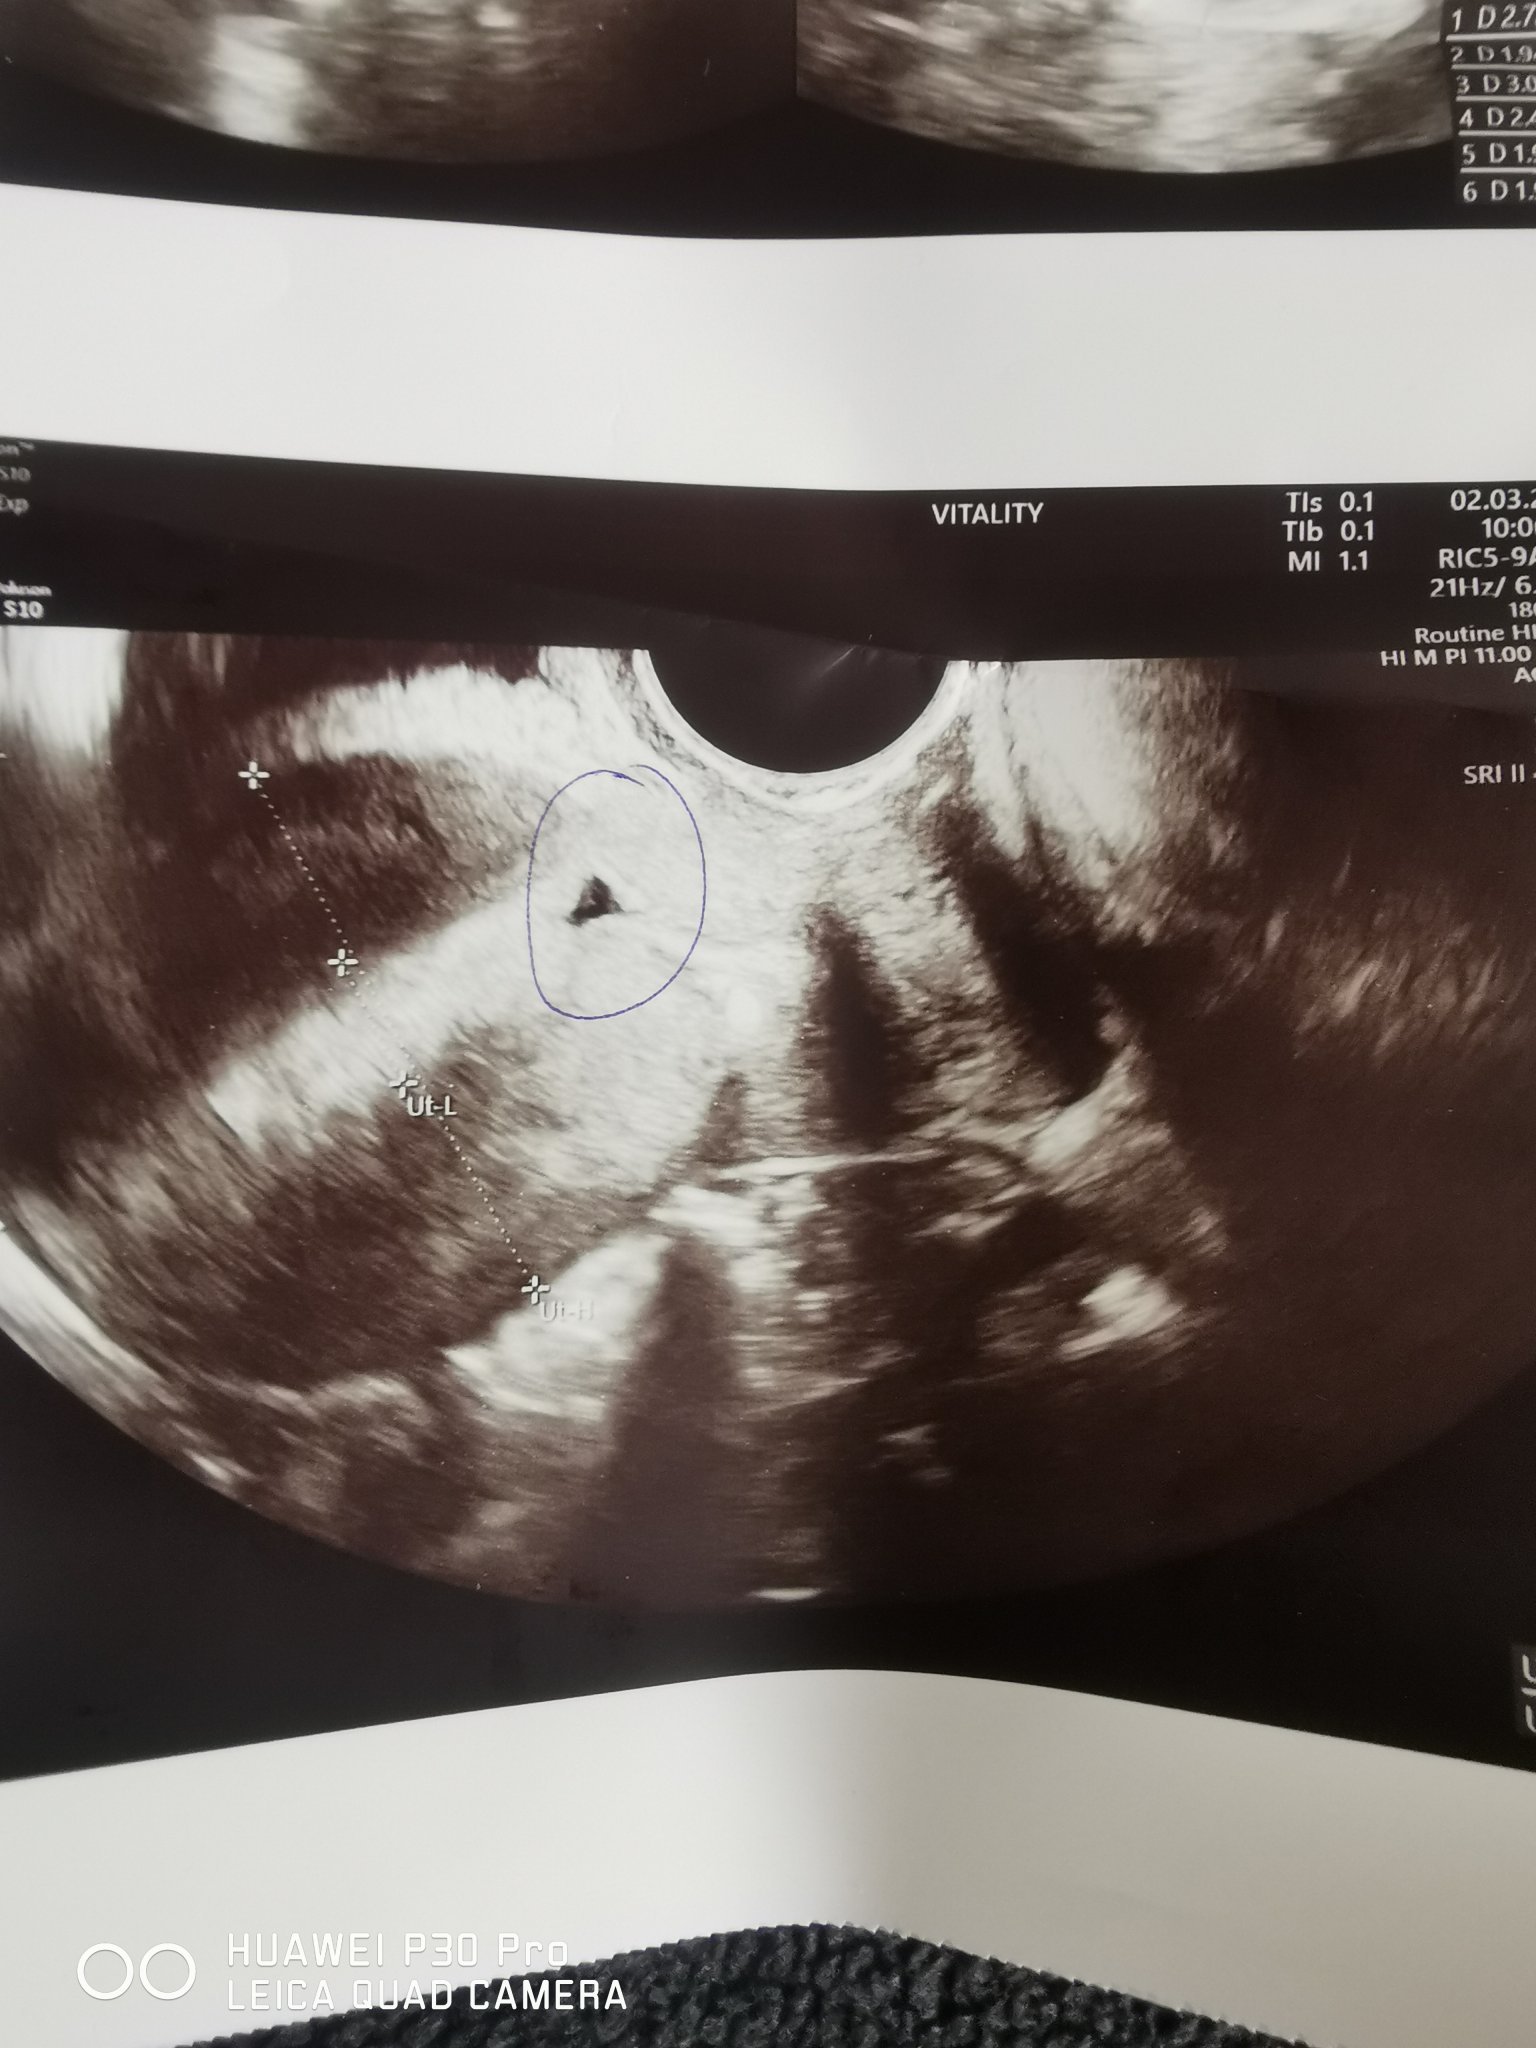

Незнам. Видя сак и бил пълен с нещо. Малък уж, вследствие на секцио. Имам снимка. Това очертаното със кръгче. Ако е това, което мислиш, не с ОК нещата.